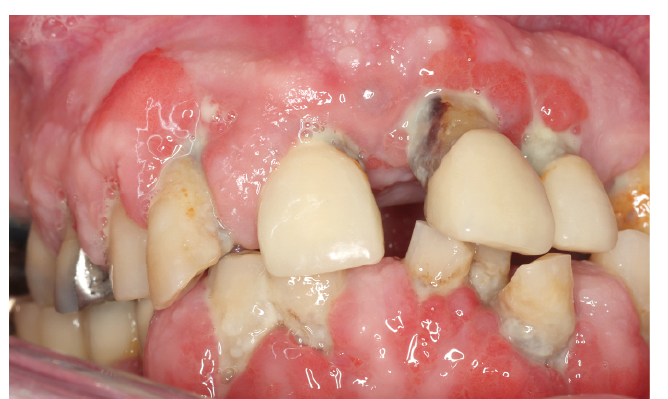

Wahrnehmungsverschiebung bei chronisch Erkrankten – der Response shift

Menschen mit Diabetes sind chronisch krank, oftmals mehrfach mediziert, haben Komorbiditäten und sind dadurch, wie viele andere Risikopatientengruppen, in einer festen Rolle („chronisch krank“). Dabei geraten bei chronisch Allgemeinerkrankten oftmals mundgesundheitsbezogene Themen nicht nur in den Hintergrund, sondern werden vielmehr auch als nicht mehr relevant empfunden. Dieser Prozess verläuft langsam und kann als Response shift beschrieben werden (34). Demnach besteht in der Patientenperspektive nicht nur oftmals kein Handlungsdruck für einen Besuch in der Zahnarztpraxis, sondern auch kein subjektiver Mehrgewinn einer zahnmedizinischen Betreuung. Dies wird insbesondere dadurch erschwert, als dass oftmals auch ein „negatives Feedback“ durch das zahnmedizinische Team erfolgt (Änderung der Mundhygienemaßnahmen erforderlich – Mehrbelastung des Betroffenen – Verstärkung des Response shift/Reaktanz, Abb. 3). Im Extremfall kann der Response shift zum völligen Neglect in Bezug auf die Mundgesundheit führen, wie der Fall in Abbildung 4 illustriert.